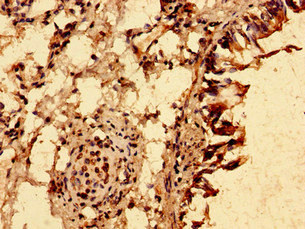

Immunohistochemistry of paraffin-embedded human lung tissue using CSB-PA024457LA01HU at dilution of 1:100